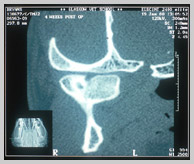

CT scan of same fractured mandibular condyle 4 weeks post-trauma